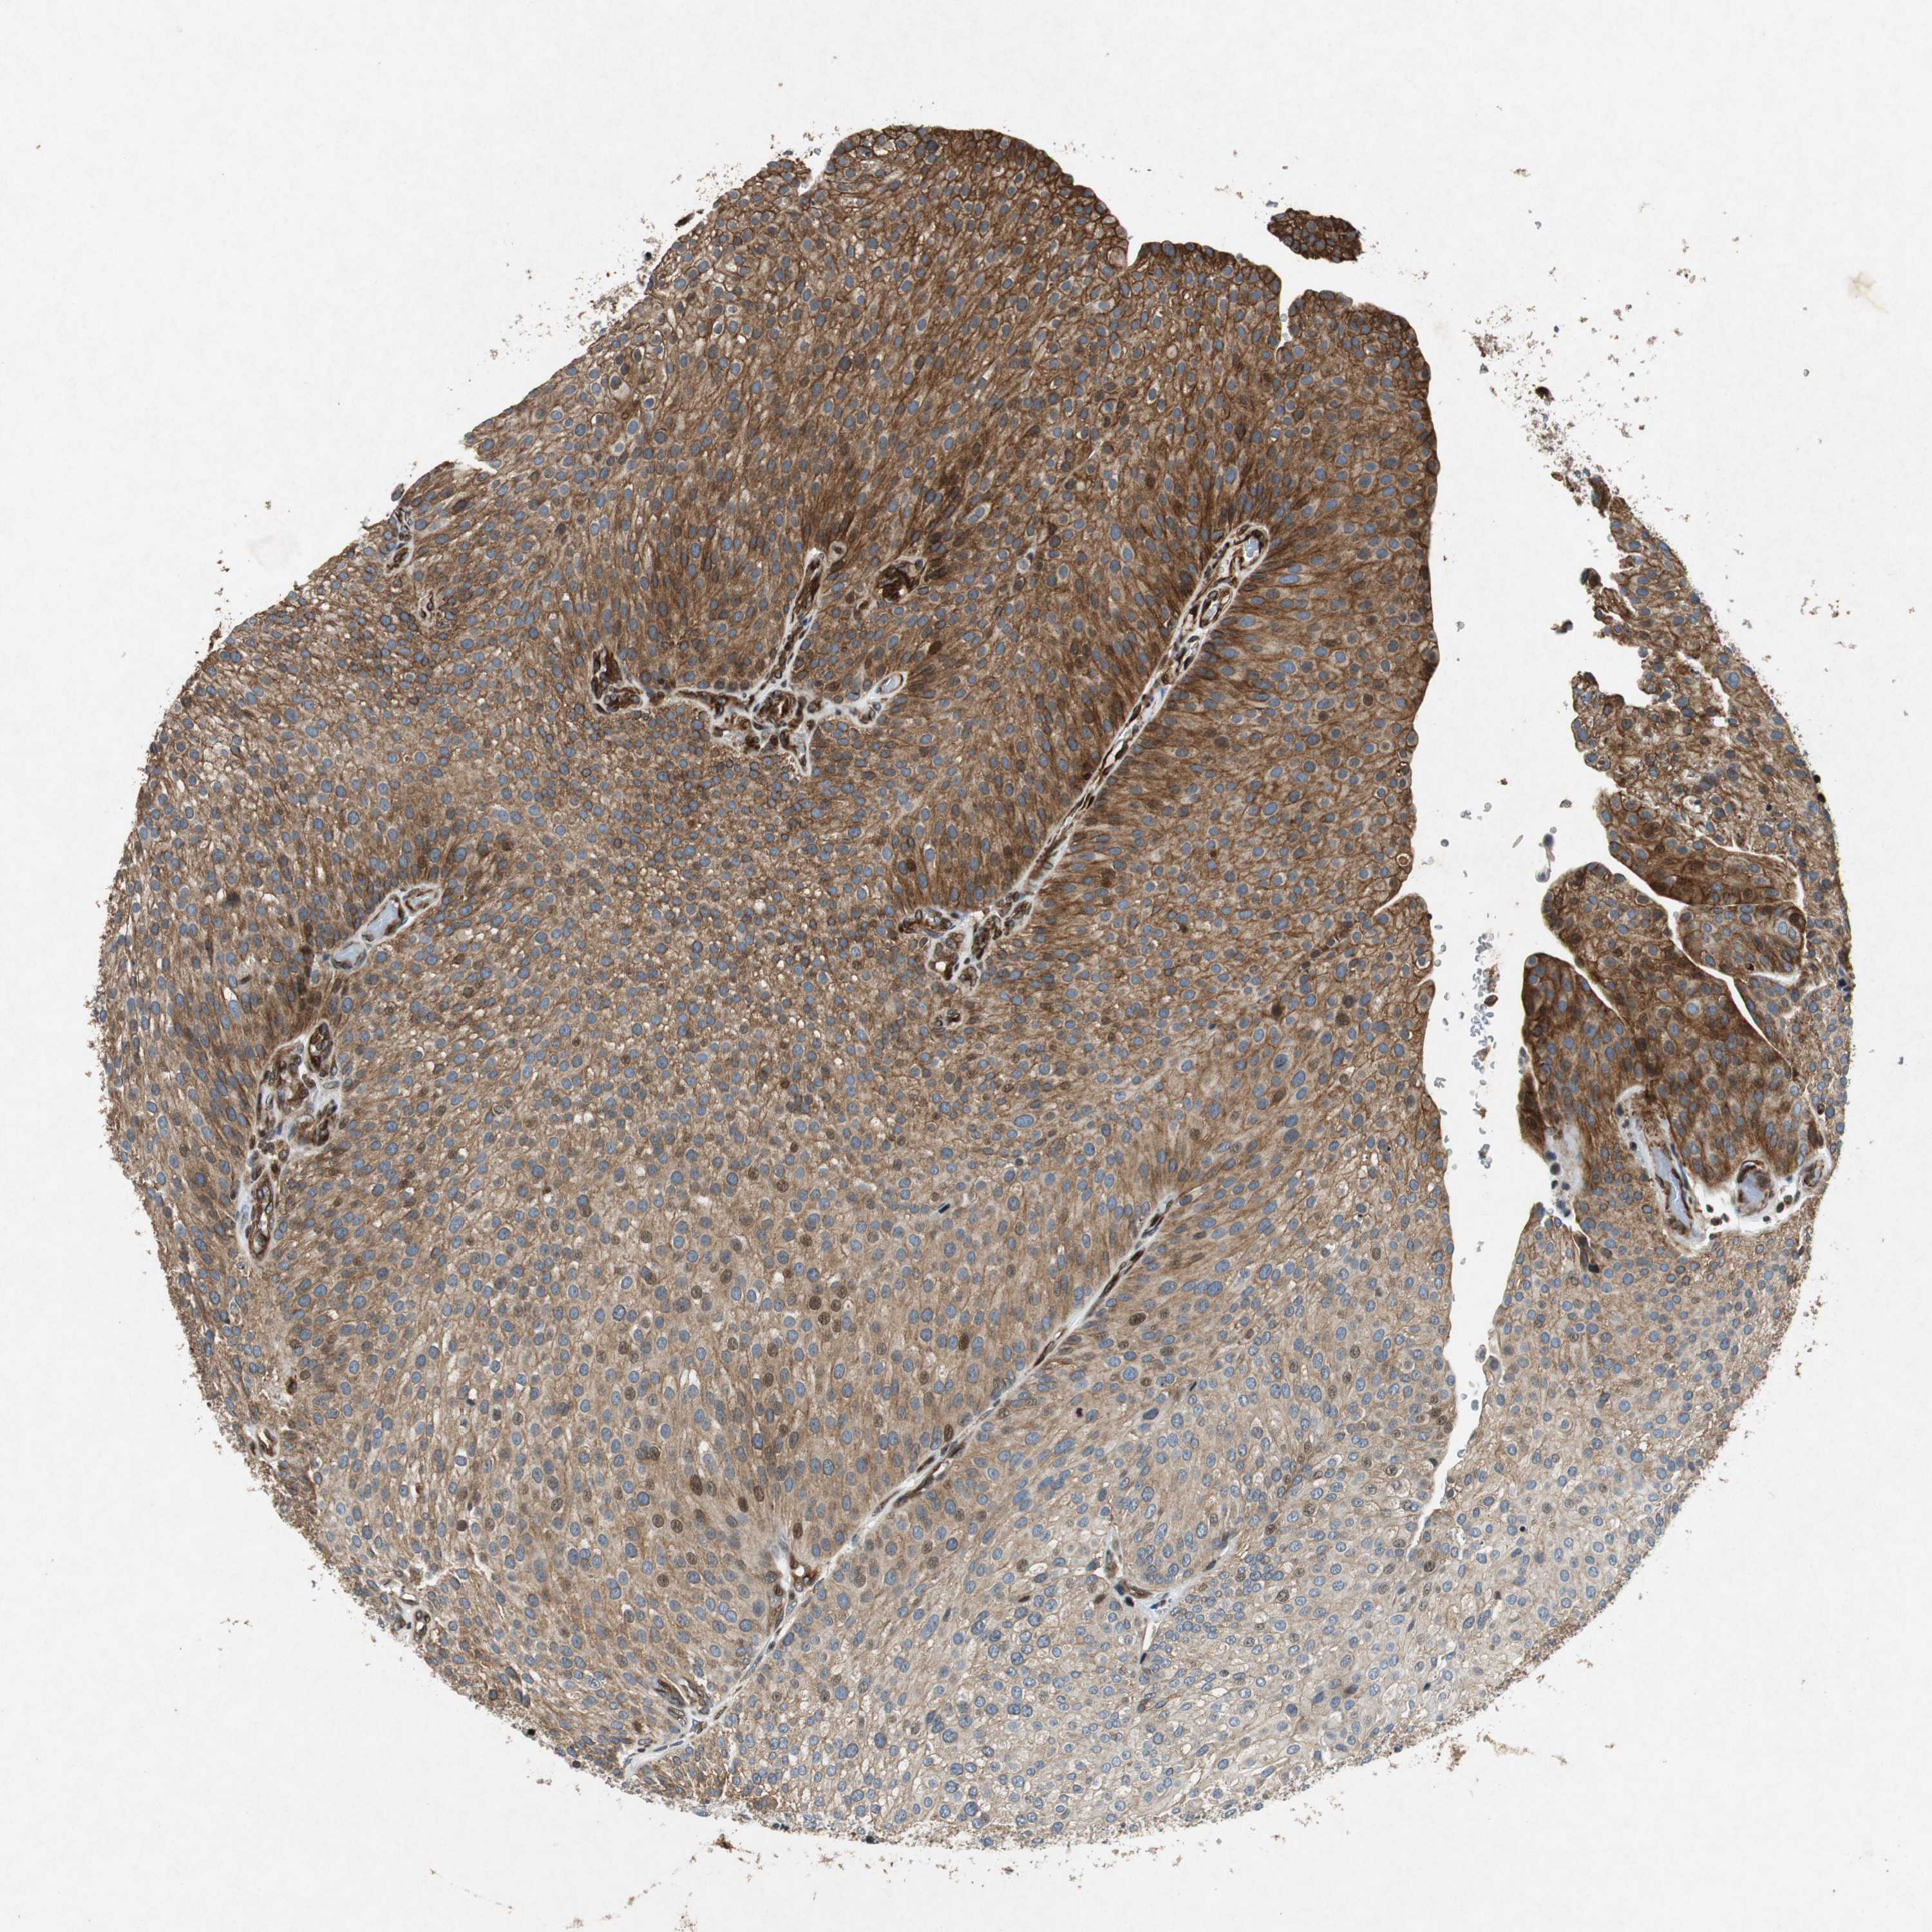

UROTHELIAL CANCER - Protein expressioni

A mouse-over function shows sample information and annotation data. Click on an image to view it in a full screen mode. Samples can be filtered based on level of antibody staining by selecting one or several of the following categories: high, medium, low and not detected. The assay and annotation is described here.

Note that samples used for immunohistochemistry by the Human Protein Atlas do not correspond to samples in the TCGA dataset.

Antibody stainingi

Antibody staining in the annotated cell types in the current human tissue is reported as not detected, low, medium, or high, based on conventional immunohistochemistry profiling in selected tissues. This score is based on the combination of the staining intensity and fraction of stained cells.

Each image is clickable and will lead to virtual microscopy that enables deeper exploration of all samples and also displays staining intensity scores, fraction scores and subcellular localization as well as patient and tissue information for each sample.

HPA039247

HPA043684

HPA063394

CAB004621

CAB005887

Staining

High

Medium

Low

Not detected

Intensity

Strong

Moderate

Weak

Negative

Quantity

>75%

75%-25%

<25%

None

Location

Nuclear

Cytoplasmic/membranous

Cytoplasmic/membranous,nuclear

Urothelial carcinoma, High grade

Urothelial carcinoma, Low grade